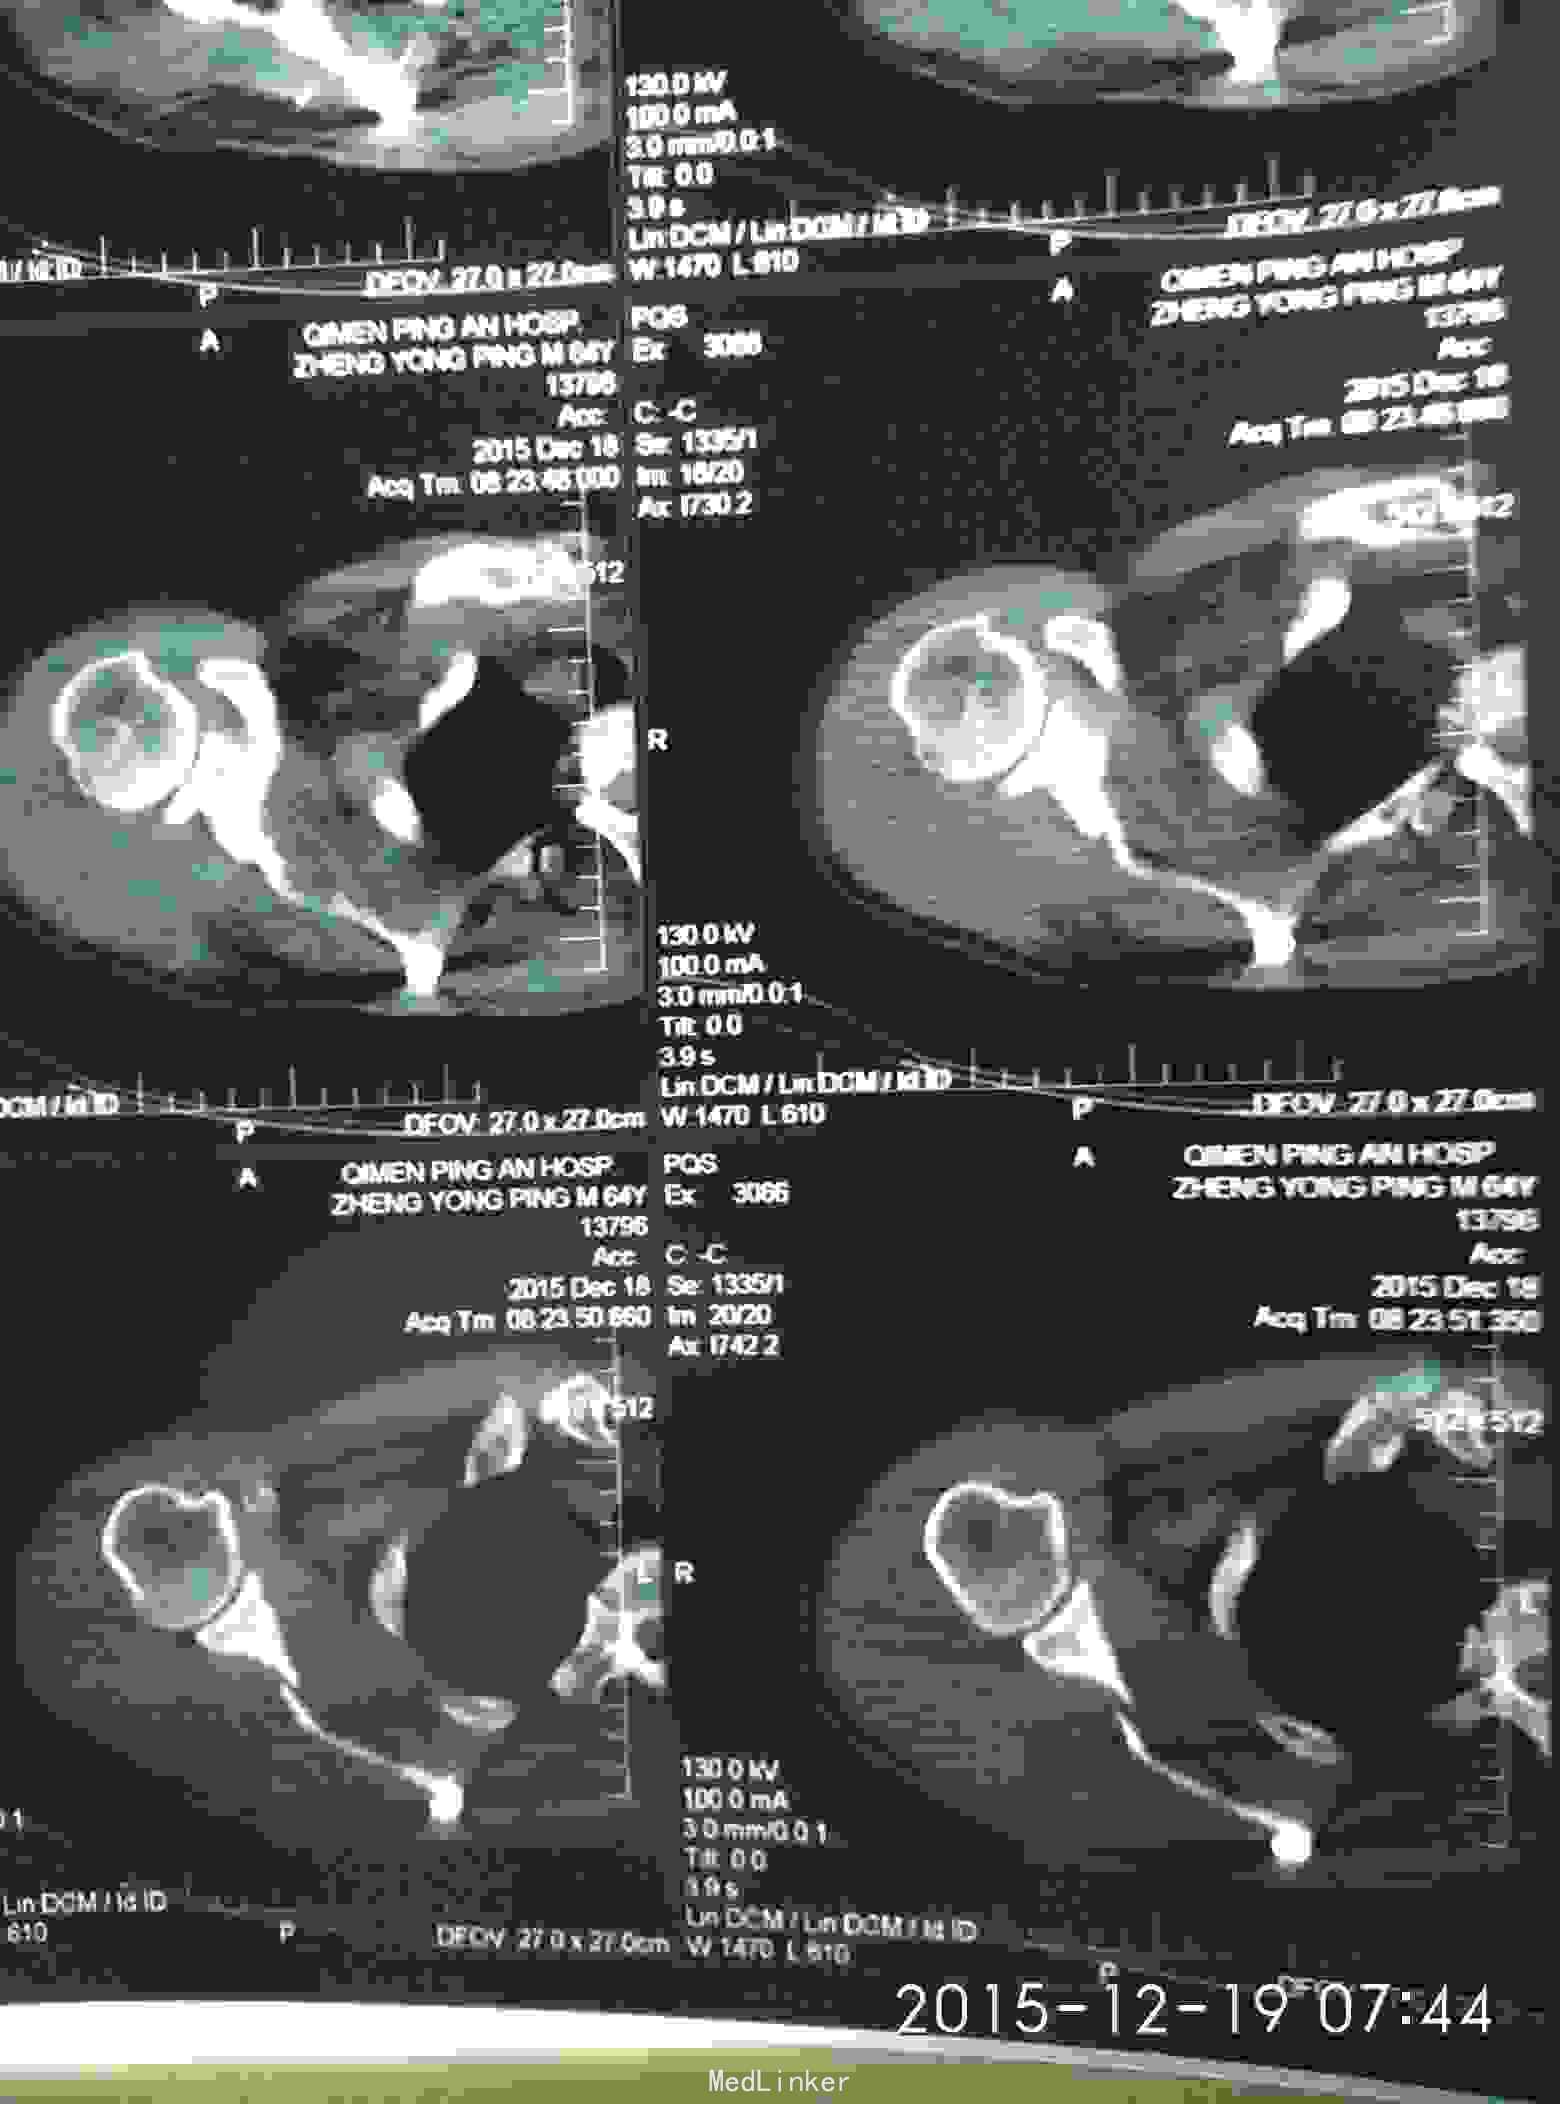

胸廓挤压试验阳性,右肩峰压痛阳性,右肩主动活动受限,外展约30度。x片及CT示右肩峰骨折及肩胛骨骨折,右第6.7.8.9肋骨骨折。

右肩峰骨折,右肩胛骨骨折,右第6.7.8.9肋骨骨折